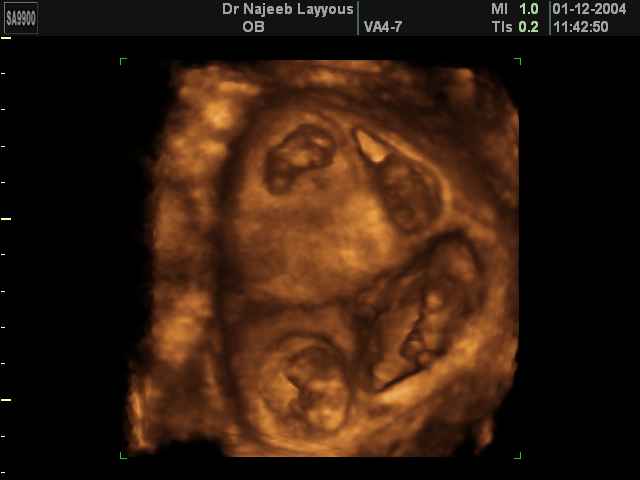

صور لتوائم بجهاز الالتراساوند ثلاثي الأبعاد | الدكتور نجيب ليوس

صور لتوائم بجهاز الموجات فوق صوتية ثلاثي الأبعاد